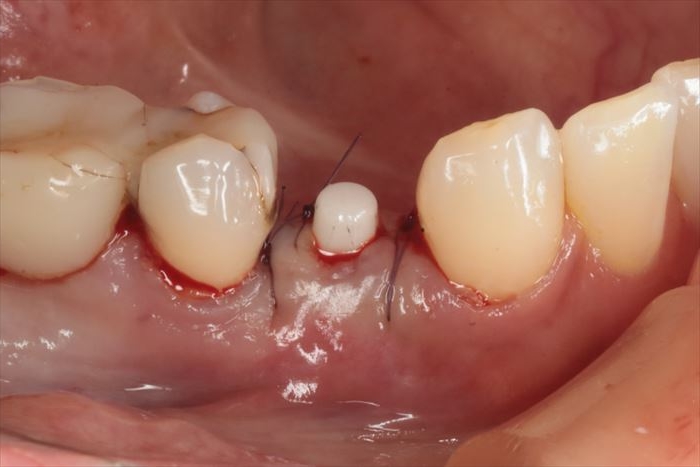

抜糸不要な吸収性縫合糸で垂直マットレス縫合しました。

_

埋入トルクは十分なことから6週後に仮歯を作成して噛めるようになります。

インプラントのネック部分をカバーするように粘膜を寄せて縫合しています。